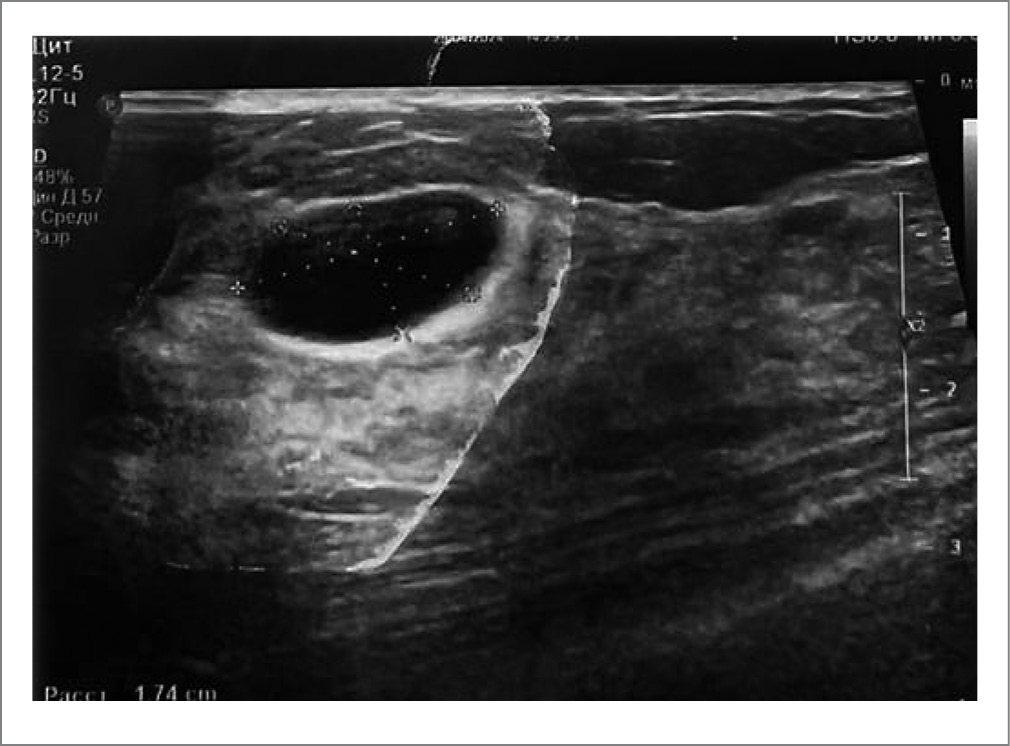

Ультразвуковые параметры ткани МЖ и кистозных образований в МЖ имели также различия между группами после лечения. В частности, до начала лечения в целом у всех пациенток наблюдалось повышение эхоплотности МЖ в сочетании с нерезко выраженной гиперплазией железистой ткани. Спустя месяц после начала терапии препаратом Мастопол® и пневмосклерозирования кист воздушной смесью у больных 1-й группы стала отчетливо прослеживаться тенденция к еще более выраженному уменьшению толщины железистой ткани и эхоплотности, а также уменьшению диаметра кист вплоть до их полного исчезновения; утончение стенок кист. В частности, сравнительный анализ медианных показателей между группами свидетельствовал о достоверном различии эхографических данных между группами (p≤0,001); табл. 1; рис. 1, 2. У женщин 2-й группы, которым проводились только аспирация и пневмосклерозирование без сопровождающей терапии, динамики в изменении структуры железистой ткани, толщины стенок кист, диаметра кист не наблюдалось. Уменьшились в диаметре только те макрокисты, из которых аспирирован экссудат с последующей пневматизацией. При этом утончения стенок кист на обнаружено. Практически всем больным 2-й группы – 89,5% (n=17) – потребовалась повторная пневматизация для полной редукции кист, тогда как в 1-й группе больных повторная пункция с пневмосклерозированием проведена только 31% (n=8) пациенток. Сравнительный анализ демонстрировал достоверное различие между группами: φ*=1,7; p≤0,04.

Рис. 2. Эхография МЖ после пневматизации.

Fig. 2. Echography of the breast after pneumatization.